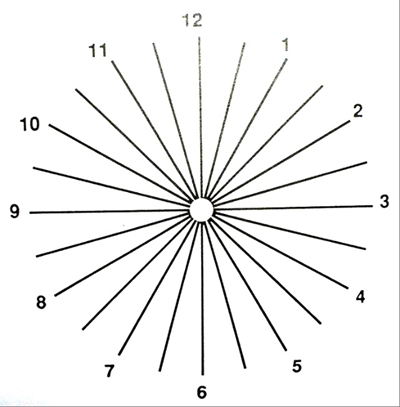

A:判斷自己有沒有散光,最簡單的方法是使用散光表來測試。散光表是一種簡單、方便的方法,但是它的準確度不是特別精確。在配鏡的情況下一般再用裂隙法,或者是交叉圓柱鏡法來精調散光的度數。散光表在網上可以看到,它類似於鐘錶的盤面,有12個數字。各個鏡線……